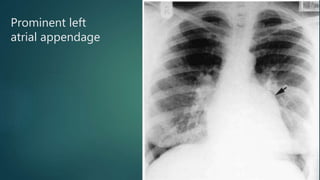

 Signs of a mitral heart:

 Cardiomegaly

 Double right heart border - due to

enlargement of the left atrium.

 Prominent left atrial appendage.

 Severe splaying of the subcarinal

angle (150 degrees) - due to

compression from enlarged left

atrium.

Prominent left

atrial appendage